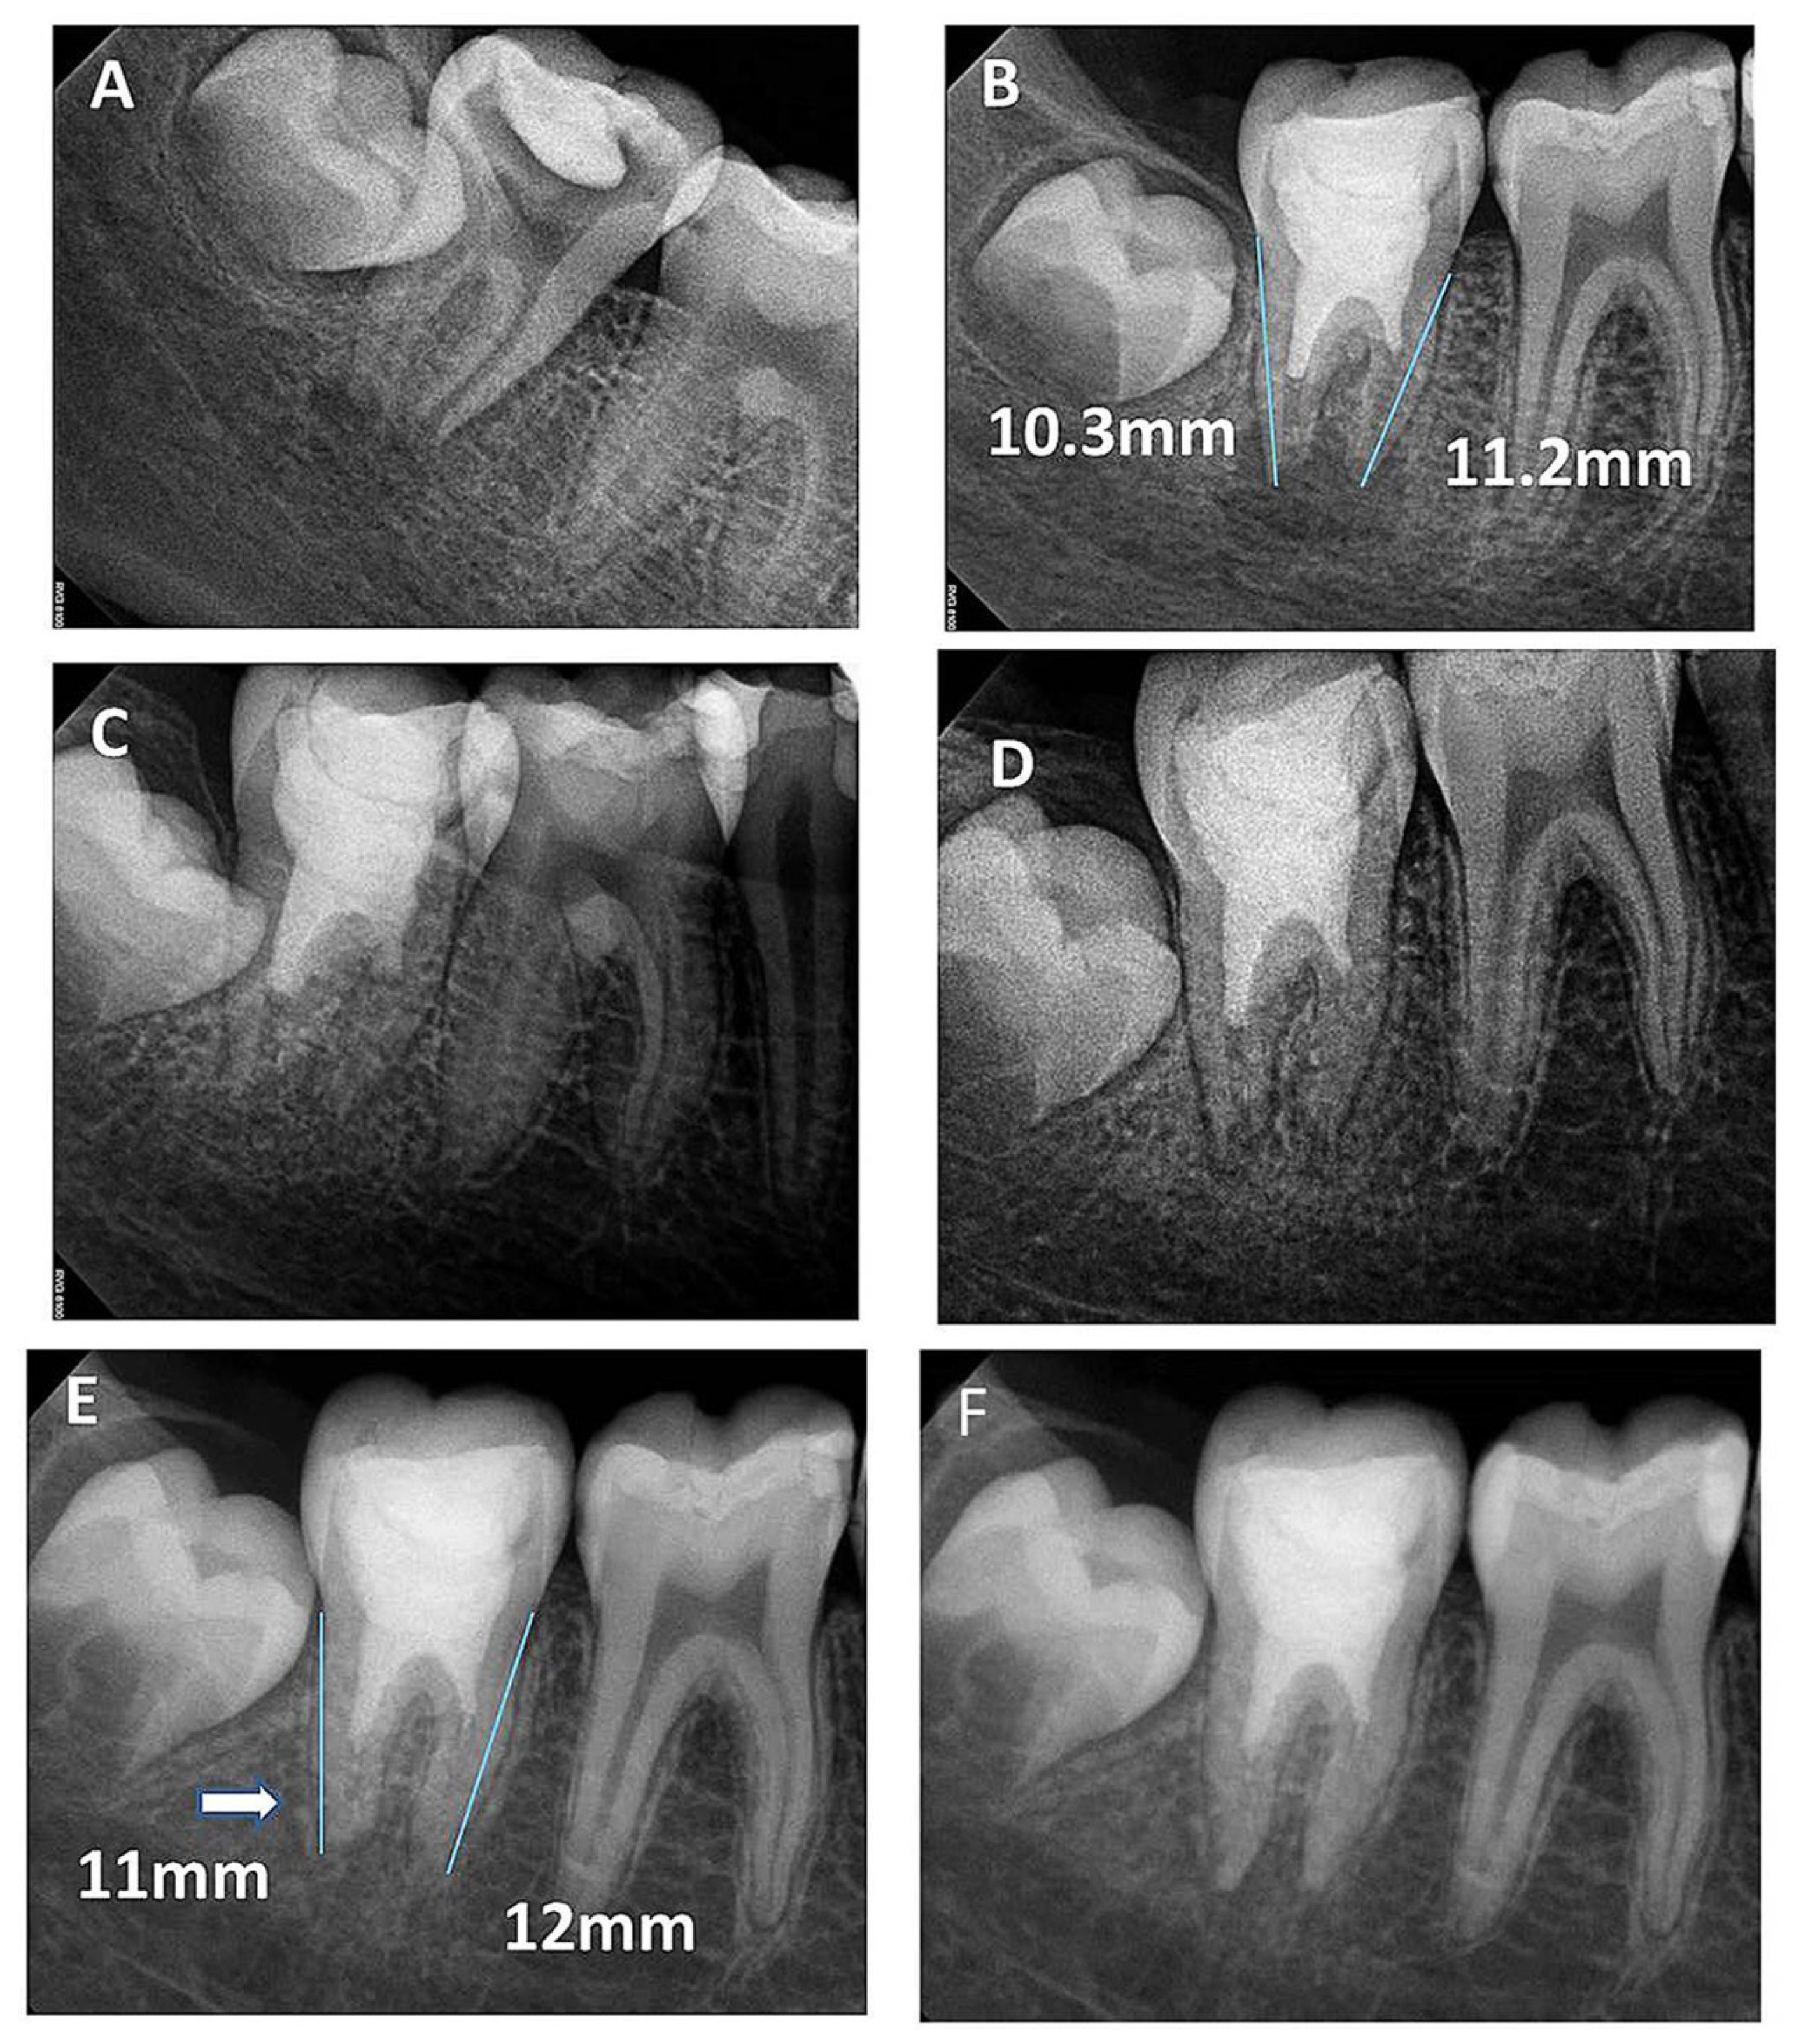

3. Results

3.1. Quantitative Assessment

3.2. Qualitative Assessment